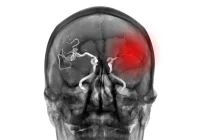

Hypopharyngeal Squamous Cell Carcinoma (HSCC) is a particularly aggressive form of head and neck cancer, often characterised by late-stage diagnosis, high rates of recurrence and poor survival outcomes. One critical factor influencing the prognosis of HSCC is lymphovascular invasion (LVI), which occurs when cancer cells infiltrate lymphatic or blood vessels. Traditionally, LVI is identified postoperatively through pathological examination, limiting its utility for pre-surgical decision-making. However, recent advancements in radiomics and imaging technologies, particularly using contrast-enhanced computed tomography (CECT), have introduced non-invasive methods to predict LVI status. They present a transformative approach to improving preoperative assessments, enabling personalised treatment planning and better patient outcomes.

Radiomics utilises advanced imaging techniques to extract quantitative features that go beyond what is visible to the human eye. In the context of HSCC, radiomic analysis of CECT scans enables the evaluation of both intratumoural and peritumoural characteristics, offering a comprehensive view of tumour behaviour. In a recent study, researchers assessed 1,648 radiomic features to develop predictive models for LVI status. These features included texture, shape and intensity metrics derived from both the gross tumour volume (GTV) and the surrounding peritumoural regions.

The study identified that radiomic features extracted from the 1 mm peritumoural region—designated as Peri1V—offered the highest predictive efficiency, with an area under the curve (AUC) of 0.94 in validation datasets. Notably, the predictive power was enhanced when these radiomic features were combined with clinical variables, forming a radiomics nomogram that achieved an AUC of 0.96. This nomogram incorporated key clinical predictors such as tumour boundaries and lymph node involvement, demonstrating the potential for integrating clinical and radiomic data to achieve superior results. Such models represent a significant advancement, reducing reliance on invasive procedures while maintaining high diagnostic accuracy.